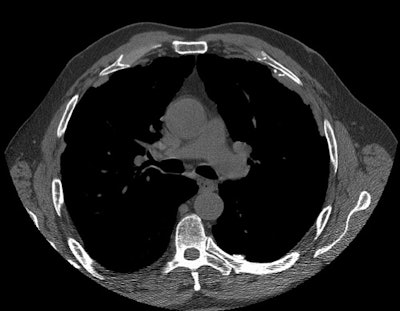

Asbestosis:

Patient with a history of asbestos exposure

The high resolution CT scan demonstrates pleural plaques- some of which contain foci of calcification.